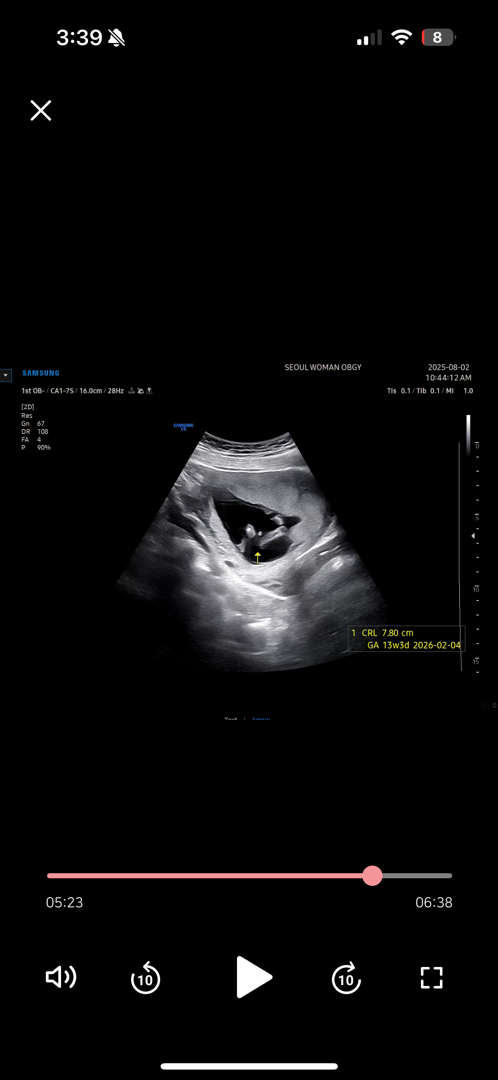

나 오늘 13주차 0일이구 각도법 볼 수 있나 엄청 공부해 갔는데 다리사이에 이거…… 확실할까 ? 🥹 나같았던 마미 있어? 14주부터 확실하다는데 희망을 놓지 말까 고수님들 도와주세요….!

13주인데 이정도되믄 확실^^ㅎ